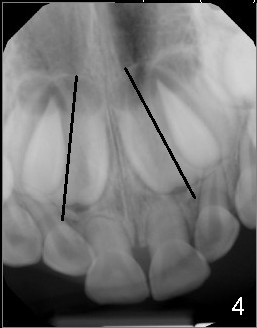

When Devon is 5 years old, there are no spaces between the deciduous teeth (Fig.4-6). The developing upper central incisors are deviated from the midline and off angle (Fig.4: black lines, as compared to Fig.1). Two upper deciduous lateral incisors are in cross bite (Fig.6). LR6 (lower right permanent first molar) rotates (Fig.7 *, as compared to normal LL6 in Fig.8).

当Devon五岁时,没有乳牙间隙(图四至图六),正在发育的恒中切牙不仅远离中线,而且角度不对(图四:斜线,与图一:8,9(恒中切牙)比较)。乳侧切牙反合(图六:D, G)。右下第一恒磨牙扭转(图七:*,与图八:左下相应牙齿对比)。